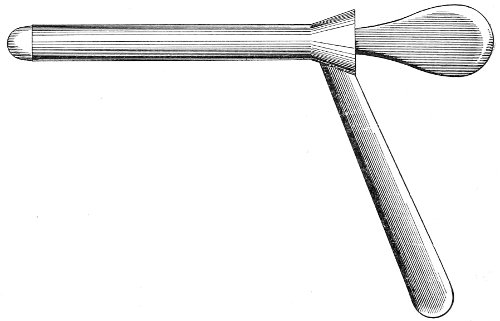

The Vaginal Speculum.—The speculum is an instrument through which a visual examination is made of the vagina, the external os uteri, and the vaginal cervix. A 29 great number of specula have been invented. At the present day the best two instruments of this class are the bivalve speculum, such as Goodell’s (Fig. 6), and the duck-bill speculum (Fig. 7), or perineal retractor, invented by Sims.

Fig. 6.—Goodell’s speculum.

The bivalve speculum is introduced with the woman upon her back, in the dorso-sacral position already described. The vulva and the vagina should be cleaned. The speculum should be warmed by placing it in hot water, and should then be lubricated with the soap solution or with vaseline. It should be introduced with the blades closed and the plane of the blades lying not exactly 30 in the median sagittal plane of the body, but inclined at a small acute angle to this plane, one edge of the speculum being directed toward either vaginal sulcus. The instrument is passed into the vagina toward the position in which, by a previous digital examination, the vaginal cervix had been found to lie. The instrument is then turned with the handles toward either thigh, so that the blades become parallel to the anterior and posterior vaginal walls, in order that, when separated, they will open the vaginal slit. The handles are brought together and the blades opened. When the vaginal cervix comes well into view the blades are fixed in place by the screws (Fig. 9).

Fig. 9.—Goodell’s speculum in position.

In some cases, where the cervix points well forward or well backward, it may be readily brought into view through the speculum by catching it with a tenaculum.

By means of the bivalve speculum we are able to make a partial inspection of the vaginal walls, an imperfect inspection of the vaginal vault, and a good inspection of the vaginal cervix and the external os. Applications 31 can be made to the cervix, but none of the minor operations of gynecology can be performed through this speculum.